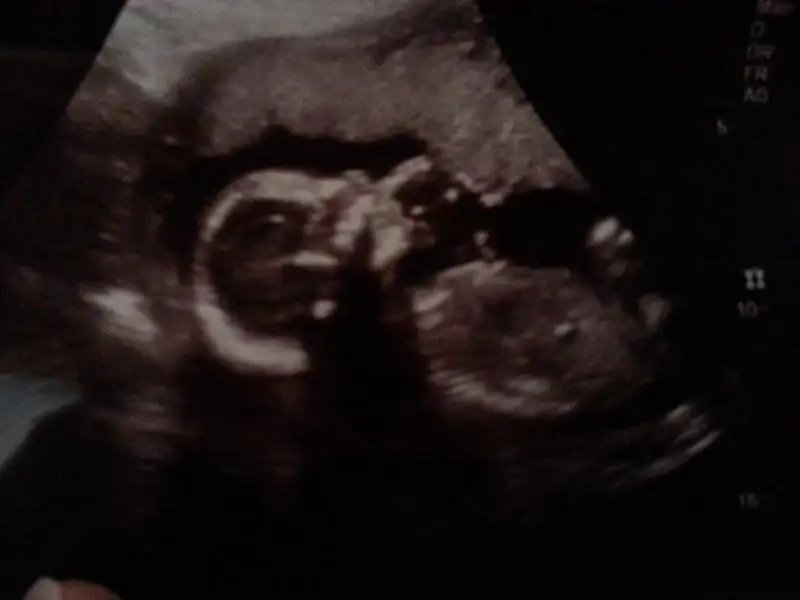

Yorumlarinizi bekliyorum...merhaba benim bebişiminde arkdaşlar cinsiyetini soyliyebilirmisiniz bn pek anlamadım kendisini göstermiyor yaramazEki Görüntüle 110894 burda 12. haftalık alttaki resim yorumlarınızı bekliyorum :)Eki Görüntüle 1108953 buda 20.haftalık suan :)

Canim doktor kiza benziyo dedi basindan beri ama yaramaz kendini gostermiyo bi turlu erkek oldugunu nerdrn anladin bakiyorum bi turlu cikartamiyorum.gonlumde hep kiz var ama saglikli olsunda :)

nubun yukarı bakması gerekiyor erkek olması için kızsa paralel oluyor.

Seninkisinde de nub görünmüyor. Ben göremedim. Kız tahmin ediyorum. Doktor ne diyor?